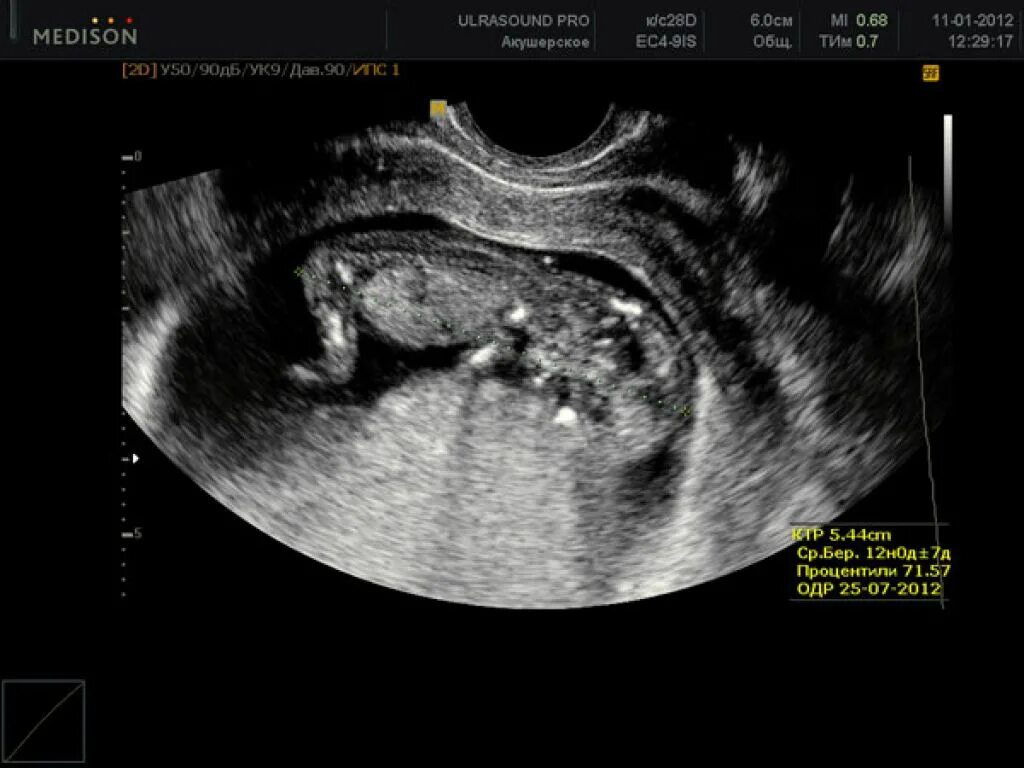

12 недель и два дня